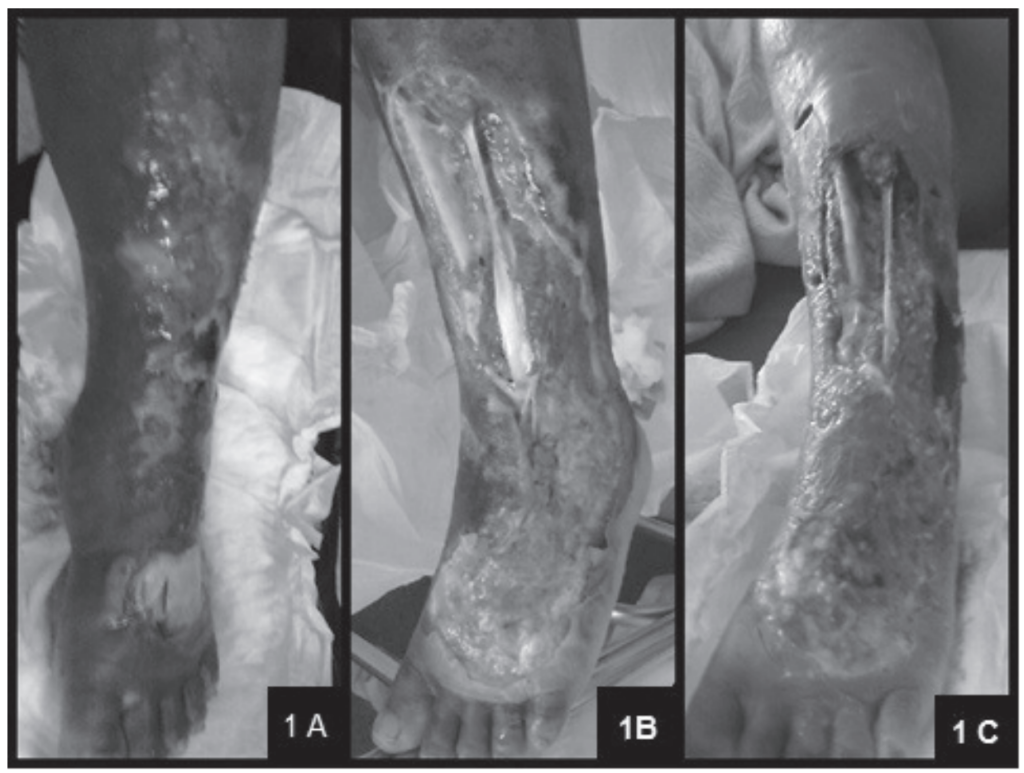

Ao ocorrer o acidente, se direcione ao centro hospitalar o mais rápido possível! Existem episódios onde a pessoa que foi mordida decide esperar para procurar ajuda médica ou é mordida por uma cobra peçonhenta e não sabe, as consequências disso são o agravamento do quadro de envenenamento podendo chegar a óbito. Seguem abaixo exemplos de acidentados: